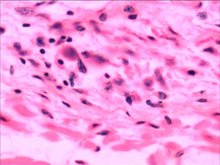

Hantavirus belongs to the Hantaviridae family under the order Bunyavirales and is an enveloped, single-stranded negative-sense RNA virus. The virus was first discovered in 1976 in the Hantan River area of South Korea, from which its name is derived. Its natural hosts are primarily rodents (such as mice), and the virus can persist in the host for extended periods without causing obvious illness. Hantaviruses are widely distributed globally, with different types of the virus exhibiting close co-evolutionary relationships with specific rodent hosts, forming complex geographic distribution patterns.

Hantavirus particles are spherical or polymorphic, with a diameter of approximately 80–120 nm, displaying typical structural features of bunyaviruses. From the inside out, the virus particle consists of three main components: the core is a helical ribonucleoprotein complex formed by the tightly bound viral genomic RNA and nucleoprotein (N protein); the outer layer is a lipid bilayer envelope composed of the viral glycoproteins Gn and Gc, with a grid-like array of Gn and Gc protein spikes regularly arranged on the envelope surface. The hantavirus genome comprises three single-stranded negative-sense RNA segments, designated as large (L), medium (M), and small (S) segments. The L segment encodes the RNA-dependent RNA polymerase (RdRp), responsible for viral genome replication and transcription; the M segment encodes a polyprotein precursor that is cleaved by proteases to produce the envelope glycoproteins Gn and Gc, which play key roles in viral binding to host cell receptors and membrane fusion; the S segment encodes the nucleoprotein (N), the main structural component of the virus particle, which plays a crucial role in viral genome packaging and host immune modulation. The Gn glycoprotein on the surface of the virus particle contains important antigenic epitopes and is the primary target of neutralizing antibodies. Hantaviruses complete their assembly in the host cell endoplasmic reticulum and are released via the cellular secretory pathway.